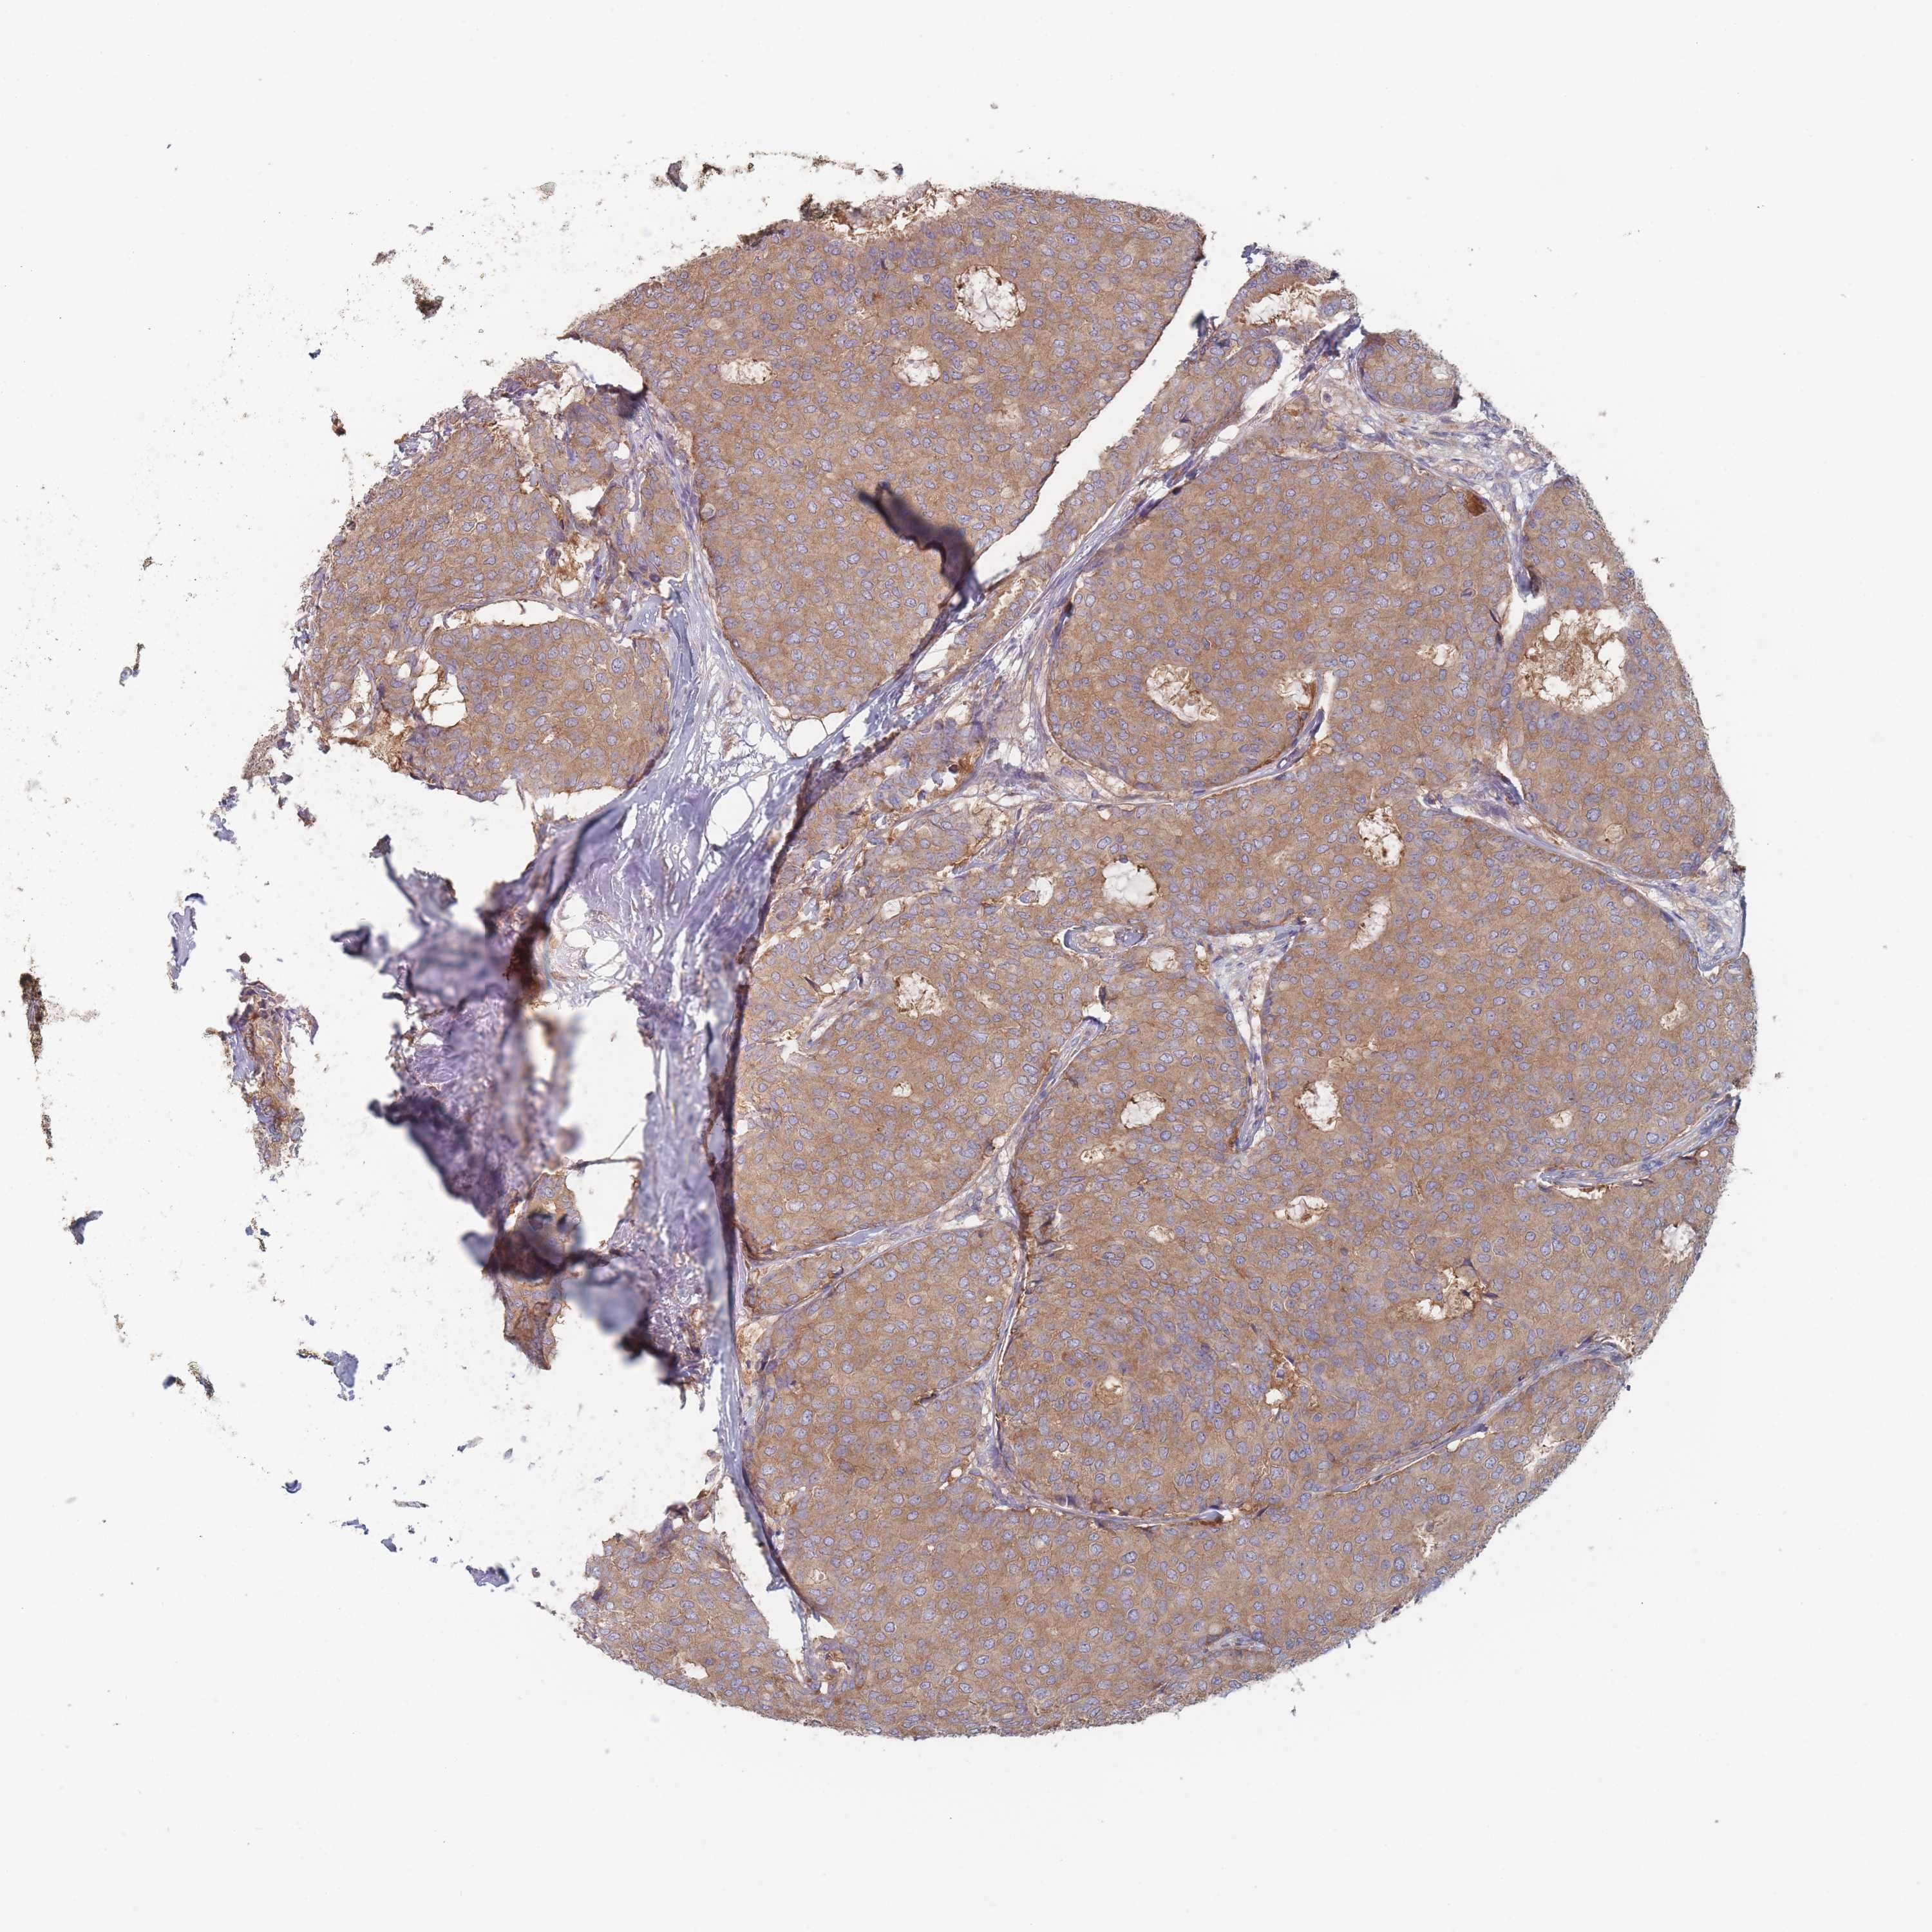

BRCA TCGA BRCA VALIDATION PROTEIN EXPRESSION

ANTIBODIES

AND

VALIDATION